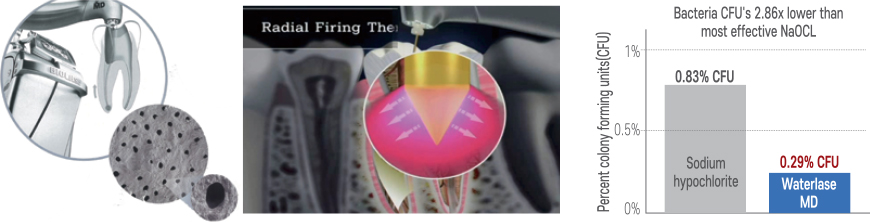

Laser Sterilization Effect

- Excellent debridement and sterilization minimize recurrence

- 10x deeper penetration than chemicals, sterilizing even accessory canals

- Superior sterilization

Achieves 2.86 times lower bacterial density compared to maximum effect of NaOCl

- Effective sterilization of resistant bacteria minimizes reinfection

Even the most resistant strain, E. faecalis, which cannot be eliminated by NaOCl, is completely removed